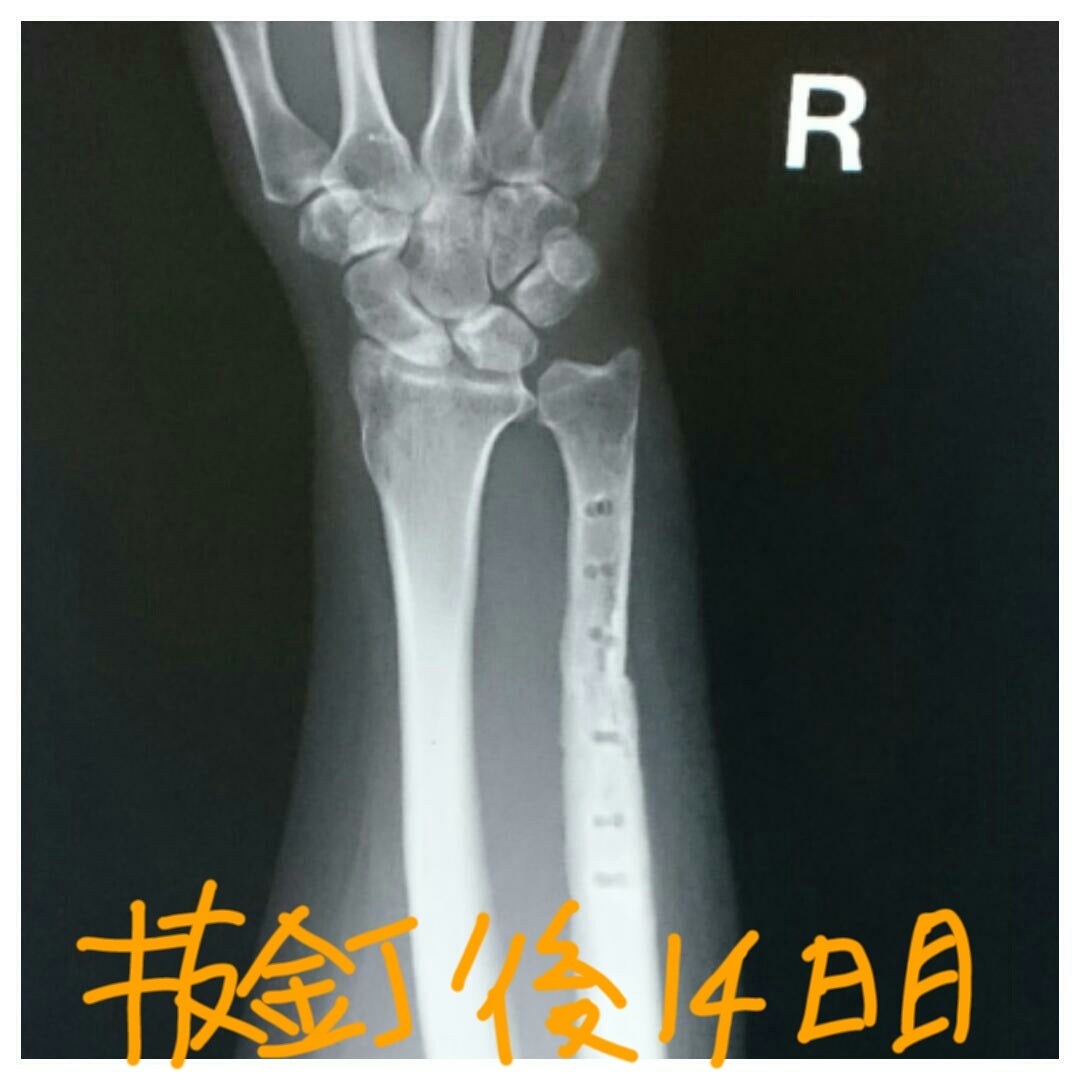

tfcc損傷と尺骨短縮術後㊻抜釘後その3ホンダのTFCC損傷と更年期主婦のブログ。

TFCC損傷尺骨突き上げ症候群druj不安定症入院手術尺骨短縮術ギプス手術跡レントゲン入院記録抜釘手術。